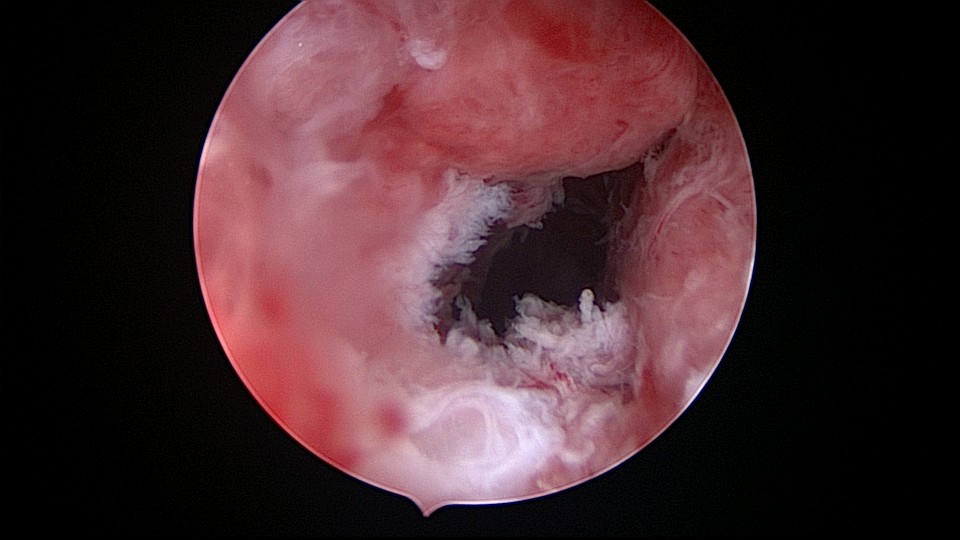

患者54岁,G2P1,顺产1次。安环26年,绝经1年,外院取环失败,子宫穿孔。宫腔镜术前B超提示子宫前位,盆腔未见异常。子宫极度前倾前屈位,宫腔下段后壁偏右穿孔,宫腔镜进入盆腔,见肠脂垂,未见积血,宫腔镜退出盆腔,寻找节育环。手术大部分时间在寻找宫颈内口和宫腔方向,在子宫穿孔的左上方找到宫颈内口,宫腔镜艰难进入宫腔,异物钳取环就迎刃而解了,取出一枚O型环。